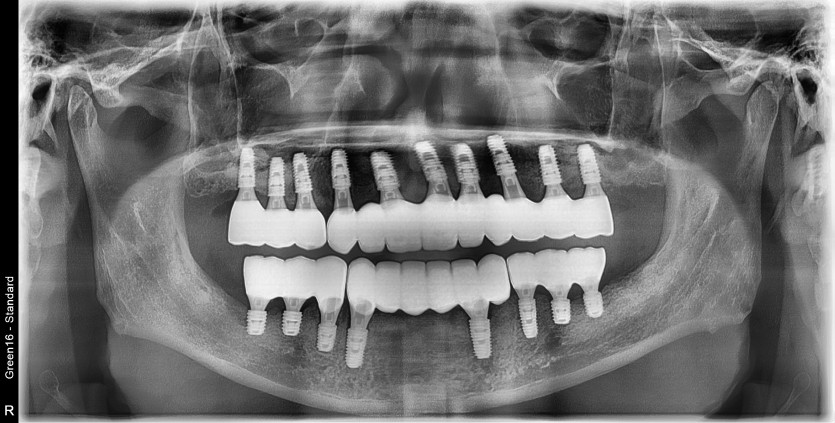

만 50세 전체임플란트 증례입니다.

전체 임플란트 증례입니다.

18개의 임플란트로 완성하였습니다.